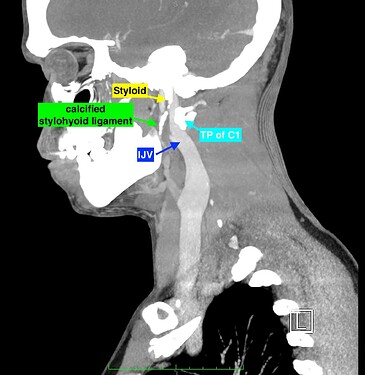

From your current description, I’d say you have internal jugular vein compression possibly being caused by your styloid/C1 & based on the pictures you posted, more by C1 (I’m assuming the sagittal image is your right side). With your note that your right external carotid artery is in the wrong place, I suspect you may also have ICA/ECA irritation/compression being caused by the right greater horn of your hyoid. The issue more likely is that the right greater horn of your hyoid is elongated & has come between your ICA & ECA just above the carotid bifurcation. We’ve been seeing more of this recently as well as having more members who seem to have symptoms & scan evidence of both ES & HBS.

I’ve annotated a couple of your images but please don’t take my guesses as diagnostic. You have lost the lordotic curve in your cervical spine which can also contribute to the symptoms you have by bringing the styloids & hyoid closer to the nerves & vascular tissues in your neck thus increasing the chance they will “meet” in an unfriendly way. There are gentle PT exercises that can help restore the curve (see the link below) or explore the Denneroll (Cervical Combination Order).